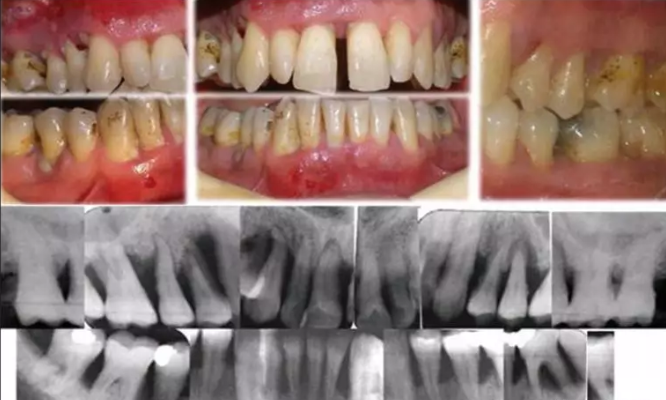

牙周炎的表现

1.牙龈出血,刷牙出血是牙龈有炎症表现。

2.持续性口臭,牙周炎引起的牙龈出血,组织发炎,致病菌产生的代谢产物都会造成口臭。

3.牙龈肿痛,牙龈上有个“大包”,也许是才起的,也许是反复肿的。这就是牙周炎症导致的“牙周脓肿”。

4.牙龈发胀、痒或不适,有些患者会感觉牙龈的某个部位有胀痒感或不适感,甚至用牙签或用手指去触碰会有舒适感,这就代表您需要专业的牙周检查和治疗了。

5.牙缝越来越大,牙周病会引起牙龈和下方牙槽骨的退缩,引起牙间本应由牙龈和牙槽骨占据的空间暴露,使患者牙缝越来越大。

6.牙齿松动甚至脱落,当您发现有个别牙齿甚至自行脱落时,一定要及时来进行牙周检查,口内其他牙的寿命就在您的一念之间。

7.牙齿尤其是上下前牙的移位,很多患者发觉自己的上前牙或下前牙在一段时间内慢慢发生了位置的改变,这是牙周炎的症状。